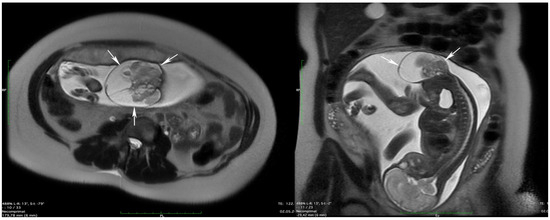

| Fetal MRI | 30th week |

|